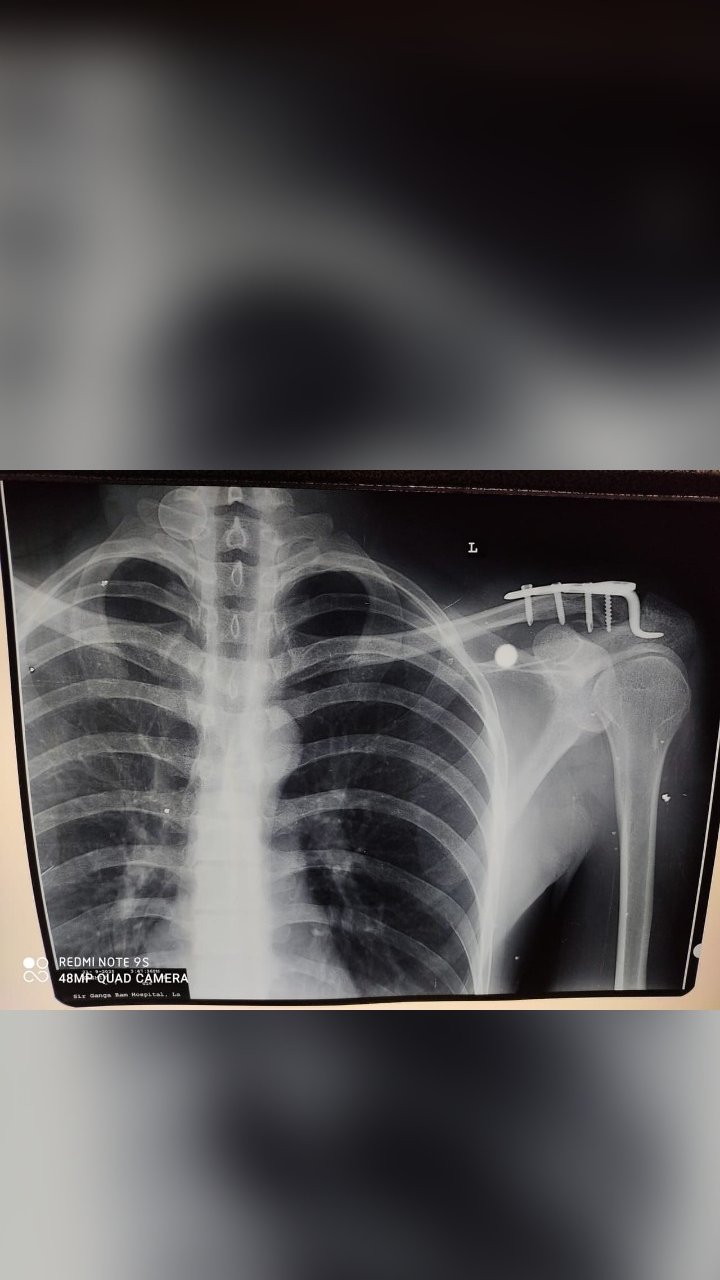

LATERAL CLAVICLE FRACTURE SURGERY

ACROMIOCLAVICULAR JOINT SURGERY